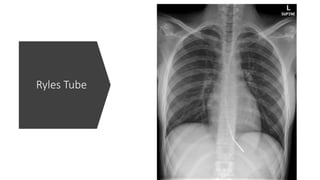

Ryles Tube

ICU – Tubesand Lines